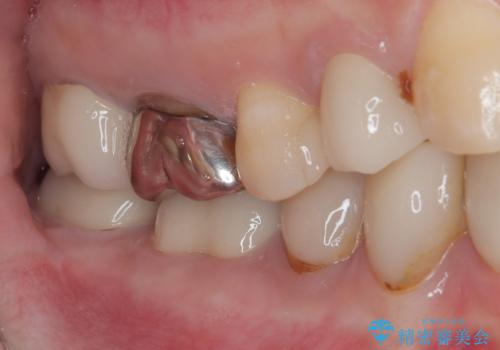

また、奥歯にも痛みがあったり治療途中で放置されていたりと、全顎的な治療が必要な状況でした。

その後、奥歯は痛みのある部分から少しずつ、根管治療やインプラント治療などを行うこととしました。

インプラントが必要となった奥歯は、インプラントが埋入できないほど隣の歯の根尖病変が非常に大きかったため、根管治療を行ったうえで半年ほど待ち、骨が再生したことを確認してからインプラントを埋入しました。期間は長くかかりましたが、大変良い仕上がりとなりました。